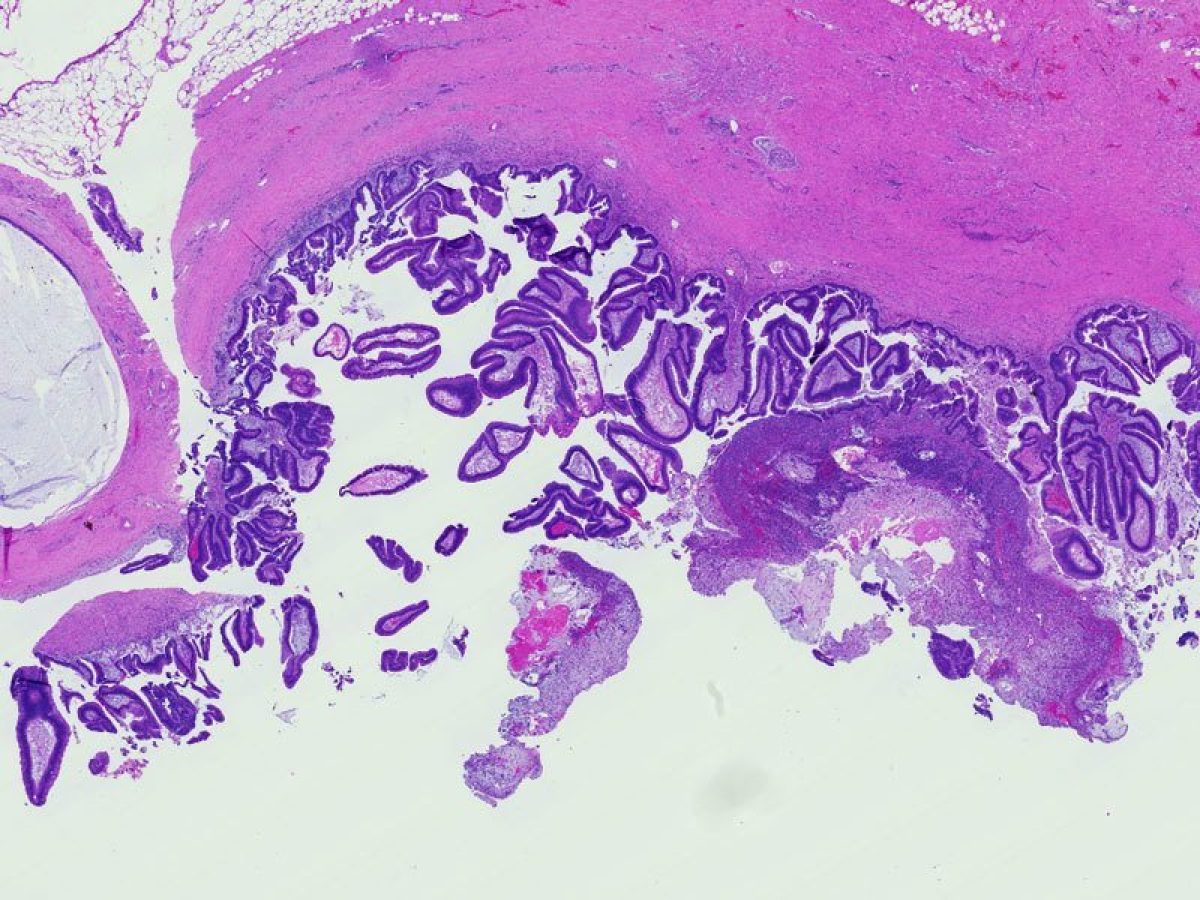

A term used to describe certain tumors which grow in finger-like projections. Pathologists use this term to describe some precancerous lesions in the pancreas (intraductal papillary mucinous neoplasm).

A fluid filled sac. Some tumors of the pancreas, including the serous cystadenomas and intraductal papillary mucinous neoplasms, form cysts. Cysts have a distinct appearance in CT scans. They are important to recognize because the treatment of cystic tumors can differ from that for solid tumors.

The form of cancer that most people are talking about when they refer to "cancer of the pancreas." These tumors account for 75% of all pancreas cancers.

Microscopically, adenocarcinomas form glands. These tumors can grow large enough to invade nerves which can cause back pain. They also frequently spread (metastasize) to the liver or lymph nodes. If this happens the tumor may be considered unresectable.